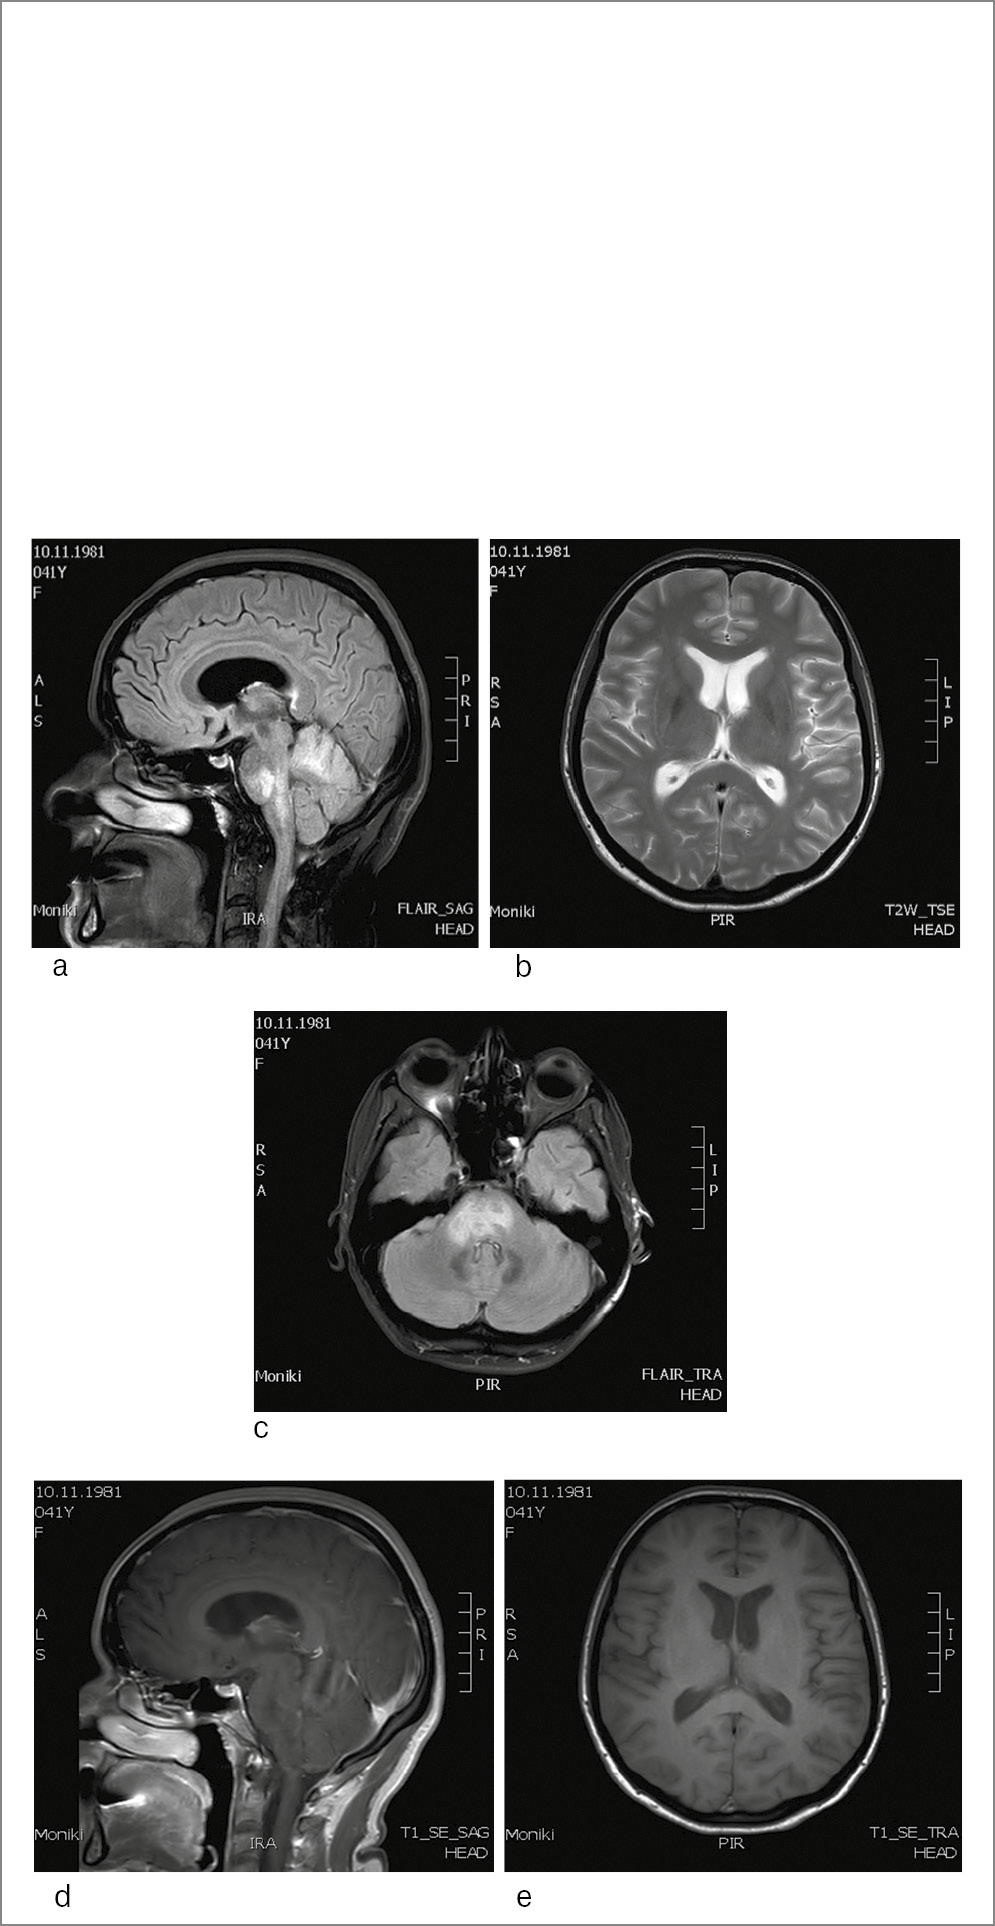

Пациентка З., 36 лет, диагноз РС, ремиттирующее течение, установлен 6 лет назад, рекомендован интерферон β-1а. На фоне проводимой терапии сохранялась активность заболевания. Пациентка переведена на ежемесячное введение НТЗ, индекс титра АТ к JCV в сыворотке крови 0,51. Состояние стабилизировалось, нежелательных явлений не регистрировалось. Проведено 18 введений и лечение НТЗ остановлено на 30-й неделе беременности (следуя рекомендациям на тот момент по ведению беременных на терапии НТЗ). Роды срочные, самостоятельные, здоровый мальчик: 3490 г, 53 см, по шкале Апгар 8/9. Выполнено МРТ головного мозга через 10 дней после родоразрешения, выявлены контрастируемые очаги на Т1-взвешенных изображениях, клинически пациентка оставалась стабильной, проведена пульс-терапия метилпреднизолоном 3000 мг на курс. Возобновлено введение НТЗ, при повторном исследовании сыворотки крови индекс титра АТ к JCV 0,44. В дальнейшем состояние оставалось стабильным, контроль крови на индекс титра АТ к JCV проводился 1 раз в 6 мес, МРТ головного мозга 1 раз в 12 мес (рис. 2). После родов пациентка получила 25 введений НТЗ (всего проведено 43 инфузии), когда при плановом исследовании анализа сыворотки крови на индекс титра АТ к JCV отмечено его повышение до 1,31. Пациентка жалоб не предъявляла, в неврологическом статусе без изменений. Выполнено МРТ головного мозга (рис. 3), заподозрена ПМЛ, лечение НТЗ остановлено.

Рис. 3. МРТ головного мозга пациентки З. с подтвержденным диагнозом НЗМ-ПМЛ. Исследование проведено на высокопольном аппарате с индукцией магнитного поля 3 Тесла. Представлены изображения в аксиальной и сагиттальной плоскостях до и после контрастного усиления: а–c – в режимах T2ВИ, FLAIR; d, e – в режиме T1ВИ. МРТ-картина многоочагового поражения вещества головного мозга супратенториальной и инфратенториальной локализации, с вовлечением в процесс мозолистого тела, без признаков нарушения ГЭБ. В сравнении с предыдущим исследованием головного мозга обнаружено появление двух крупных очагов в правых отделах продолговатого мозга и варолиева моста и двух диффузных зон в субкортикальных отделах височно-затылочных областей обоих полушарий большого мозга, не накапливающих контрастное вещество.

Анализ СМЖ оказался невоспалительным, методом ПЦР обнаружены ДНК JCV 2568 копий/мл. Таким образом, у пациентки с длительным приемом НТЗ более 2 лет, с индексом титра АТ к JCV 1,31, отрицательной динамикой при нейровизуализации, подтвержденной исследованием ликвора, диагноз «РС, ремиттирующее течение; НТЗ-ассоциированная ПМЛ».